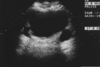

type of renal mass

anechoic, smooth walls, posterior enhancement

A

cystic

name that pathology

Unknown origin

Serous fluid collection originating in the renal cortex

Uncommon before 40 years

Found in 50% of people over 50 years old

May be multiple (rarely more than 4 per kidney

simple cyst

they are unilocular